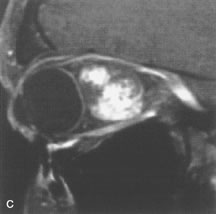

Cavernous hemangiomas appear as well-circumscribed, smooth, usually intraconal masses that are isointense to muscle on T1-weighted images and hyperintense on T2-weighted images (Fig. 12). Patchy early enhancement is typically followed by diffuse, more homogeneous enhancement.39 The internal architecture of the mass, including septation and internal vasculature, may often be appreciated with high-quality orbital imaging.40

Fig. 12. A. T1- and (B) T2-weighted MR scans demonstrate a well-circumscribed intraconal mass causing severe optic nerve displacement. These lesions are usually intermediate in signal intensity on T1-weighted scans and very hyperintense on T2-weighted Images. C and D. Postcontrast fat-suppressed T1-weighted scans demonstrate characteristic patchy intense enhancement that becomes more complete from the initial postcontrast scan (C) to a more delayed scan (D).